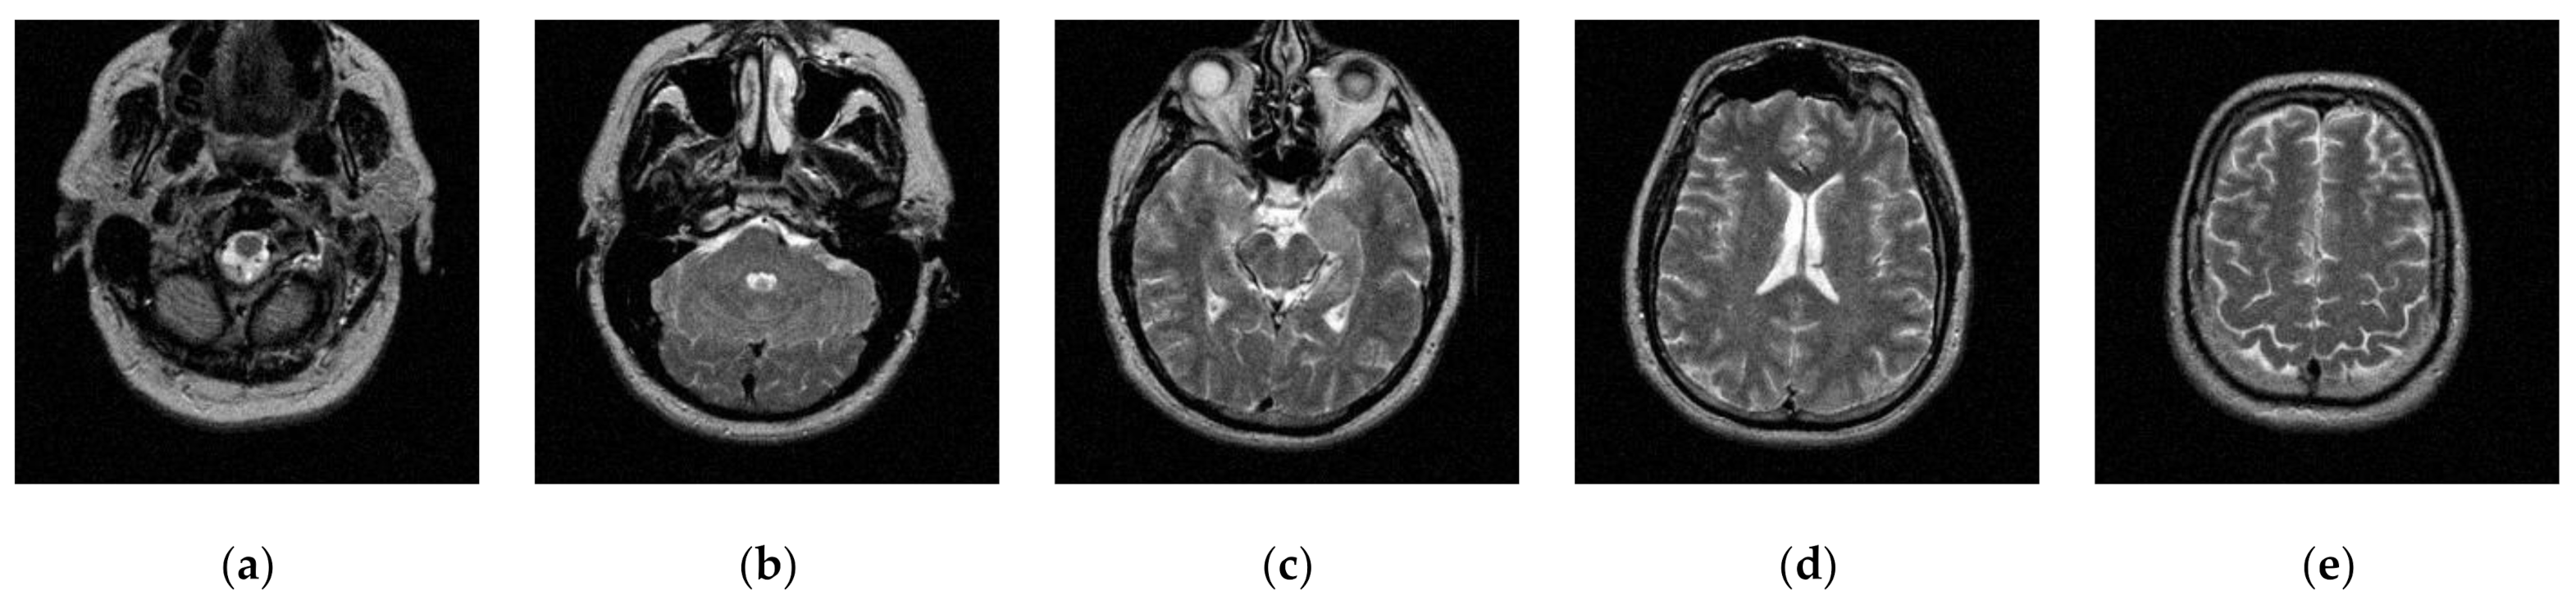

Transaxial MR-T2 brain images with various slices downloaded from “The Whole Brain Atlas” of Harvard Medical School (http://www.med.harvard.edu/aanlib/home.html, accessed on 17 May 2021) were used in the segmentation experiments. Because space is limited, the ten brain slices #022~#112 displayed in Figure 9 were chosen to demonstrate the performance of our proposed algorithm. Parameters for the proposed algorithm are listed in Table 1. All experiments were performed on a computer with Intel(R) Core(TM) i7-7500U CPU, 2.70 GHz, 8GB RAM, Windows 10 using MATLAB 8.1.0.604 (R2013a).

Figure 9.

MR-T2 brain slices: (a) slice #022, (b) slice #032, (c) slice #042, (d) slice #052, (e) slice #062, (f) slice #072, (g) slice #082, (h) slice #092, (i) slice #102, (j) slice #112.